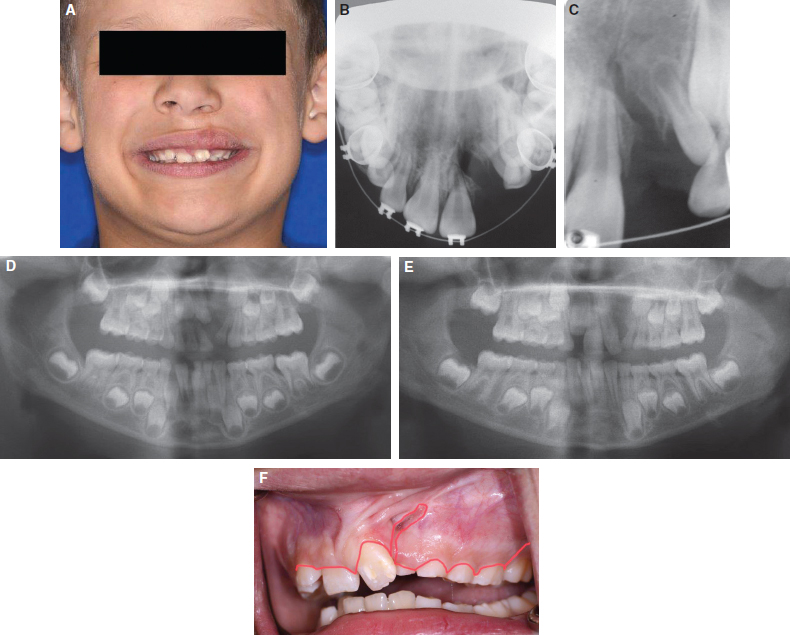

Clefting of the maxilla and alveolus results from a failure of fusion of several key components of the facial structures during the first trimester and typically includes components of the maxillary processes, median nasal process, and palatal shelves.1 When one or several of these components fail to fuse, a variety of clefts can be seen. Each bone and soft tissue defect is reconstructed in a particular fashion and is staged based on growth, functional needs, and aesthetic concerns. Despite successful lip repair and closure of the hard and soft palate during infancy, a residual nasolabial fistula and bony cleft defect that involves the alveolar ridge, maxilla, and piriform rim will remain.2,3 These residual deformities are most often addressed by secondary bone grafting performed during the mixed dentition stage of middle childhood (6 to 10 years of age).2,3 The objectives of bone graft reconstruction of the cleft maxilla are to establish adequate bony matrix for eruption of the permanent cuspid tooth, to close any residual alveolar oronasal communication, to establish continuity of the maxillary ridge, and to improve the underlying support of the nasal base (Fig. 69-1). In the case of bilateral cleft lip and palate, an added benefit of bone graft reconstruction is stabilization of a mobile premaxillary segment.

Fig. 69-1 This child with a left unilateral cleft of the lip and palate exhibits the typical depressed piriform rim and maxilla in the area of the bony cleft. Although rhinoplasty can be used in an attempt to provide symmetry to the nose, the primary lack of structure is associated with the maxillary and alveolar cleft. The defect in the bone at the alveolar level may be fairly small, but attention is required at the remainder of the maxilla to provide an adequate reconstruction to achieve all of the goals. Note the proximity of the central incisor to the cleft.

In addition, if the central incisor is bordering the cleft, some consideration can be given to earlier-than-typical grafting to provide adequate periodontal support to this area (see Fig. 69-1). Some literature supports this technique, because the periodontal outcomes have been reported to be improved. No randomized or controlled studies, however, have shown this to be an improved protocol in a comparative fashion. As with gingivoperiosteoplasty, bone retention and bone heights have been shown to be quite good in the initial reports from those who favor this approach, but the comparative studies using this protocol are still lacking.